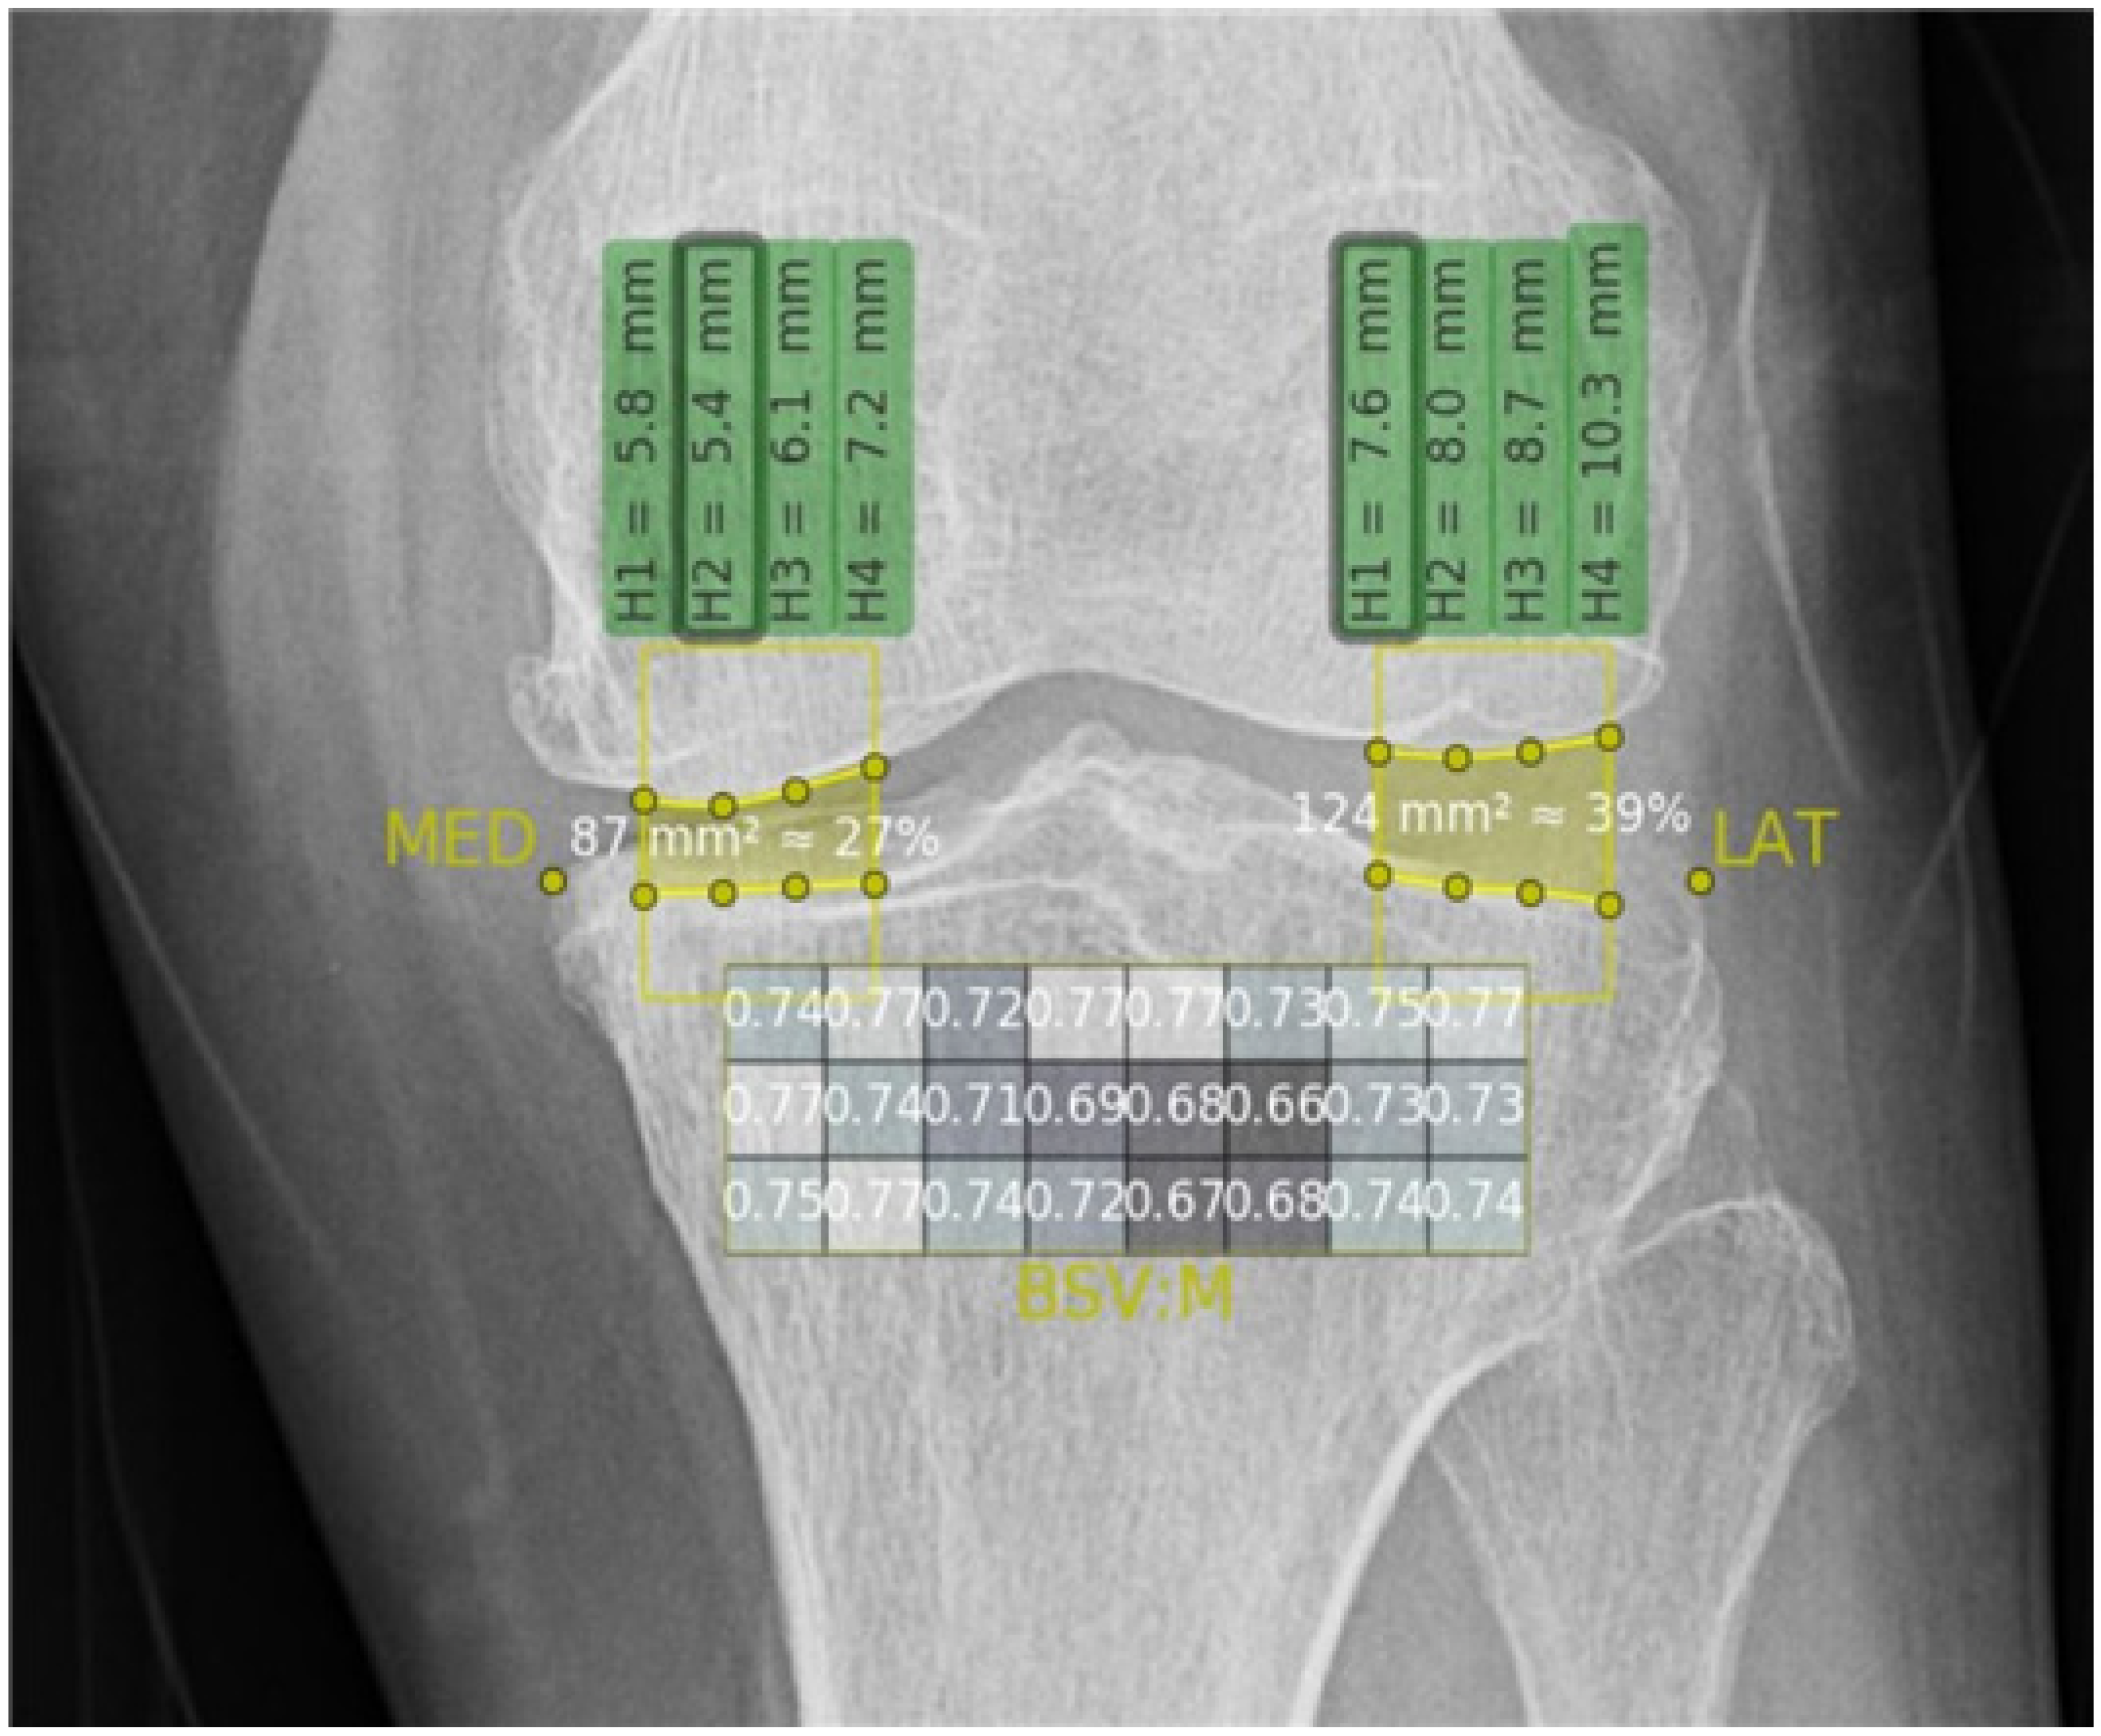

2.4.2. Texture Analysis

3.3. BSVs